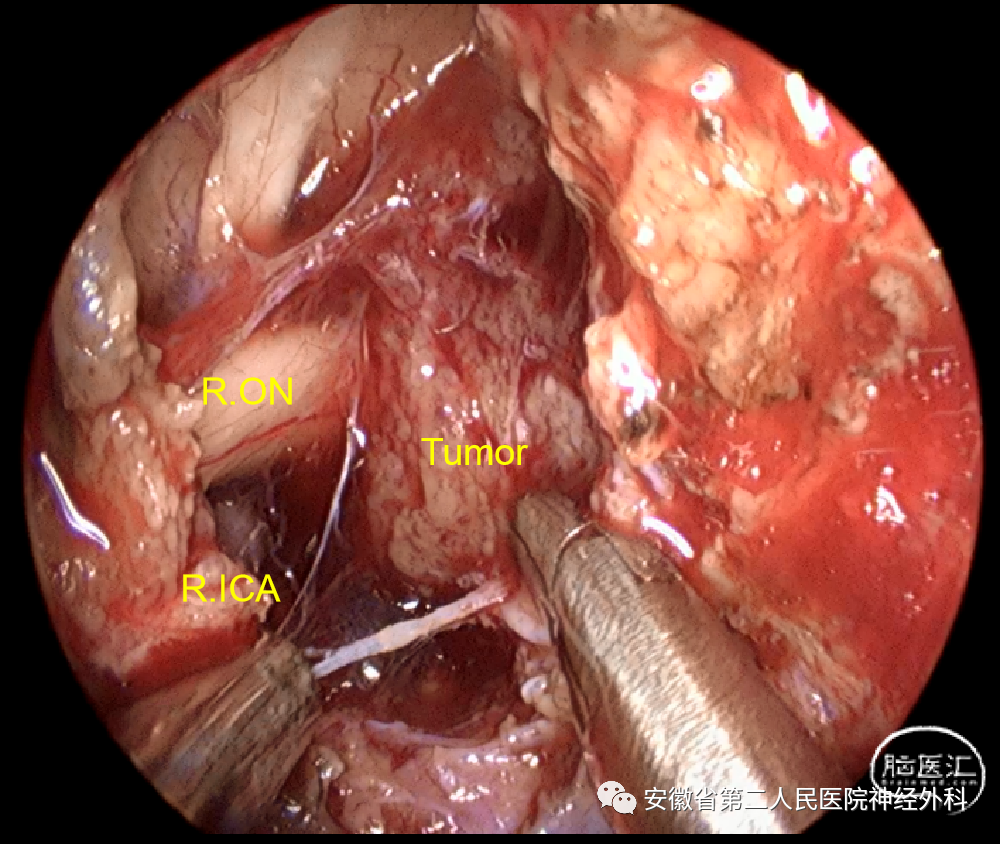

应用双鼻孔通道及双人四手操作技术,在神经内镜辅助下进行精细的显微操作并完整切除肿瘤,对于功能性垂体瘤亦可做到假包膜外切除,让患者术后激素水平达到生化缓解,真正的治愈。

经鼻蝶扩大入路(EEA)切除肿瘤,可以优先断除肿瘤基底和肿瘤血供,再锐性分离肿瘤与神经、血管的粘连,最后采用带蒂黏膜瓣、阔筋膜、脂肪、人工硬脑膜进行颅底重建和脑脊液漏修补,目前针对绝大部分鞍结节脑膜瘤经鼻蝶扩大入路因其创伤性、术后恢复快、术中可以优先断除肿瘤基底血供的特点,已逐渐开始替代传统的翼点、额外侧开颅手术。